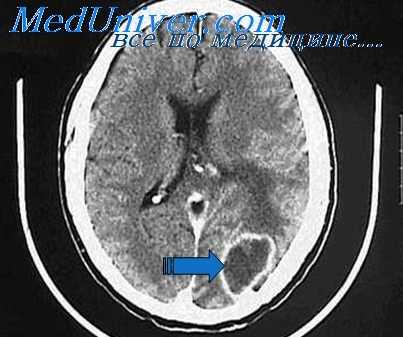

КТ при субдуральном абсцессе головного мозга

Диагностика. Важное значение для установления диагноза имеет КТ, которая позволяет также судить о поражении кости. При поражении мягких тканей, например при тромбозе пещеристого синуса, более информативна МРТ. Наиболее информативными методами диагностики абсцесса и опухоли головного мозга являются МРТ и КТ с введением контрастного вещества. При подозрении на менингит выполняют поясничную пункцию.

Диагностика. КТ и МРТ с введением контрастного вещества; неврологическое исследование; ЭЭГ; каротидная ангиография.